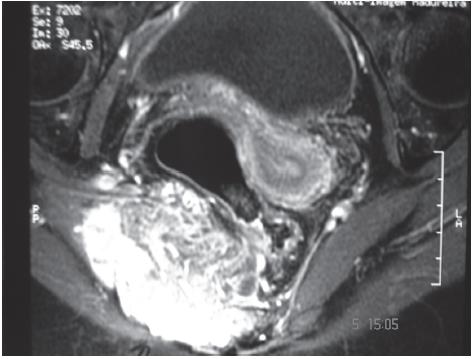

Após revisão dos prontuários, foram excluídos 21 doentes e alocados para a presente análise 15 com cordomas de topografia sacral histopatologicamente documentados. Nove doentes (60%) eram do sexo masculino e a idade variou 26 a 85, com mediana de 58 anos. Os principais sintomas foram dor (60%) e tumoração em região sacral. A tomografia computadorizada e a RNM (Figuras 1 e 2) foram diagnósticas em todos os casos.

Fig. 2 - RNM de paciente do sexo feminino no plano axial utilizando sequência ponderada em T1 com supressão de gordura, após a injeção venosa de meio de contraste. Processo expansivo parassagital direito centrado em S1-S2, com extensão anterior para a pelve e fossa obturadora, de limites mal definidos, determinando desvio anterior e compressão do reto, intensamente impregnado pelo meio de contraste.